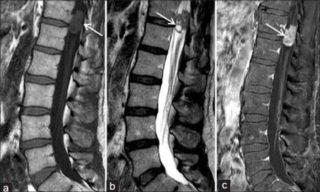

Остеохондрома

Остеохондрома — доброкачественное образование, возникающее в процессе развития скелета. Она поражает детей и молодых людей в возрасте от 10 до 25 лет. Размер остеохондромы может достигать 12 см. Образование не вызывает дискомфорта на начальных стадиях. Однако по мере роста оно может воздействовать на сосуды и нервные окончания. При пальпации определяется плотное, безболезненное образование. Кожа над ним не гиперемирована, а местная температура остается в пределах нормы.

Остеохондрома в крестцовом отделе позвоночника

Фиброма — доброкачественное образование круглой формы, состоящее из соединительной ткани и фибропластов. Она формируется в глубоких слоях дермы. Риск перерождения фибромы в злокачественную опухоль минимален. Внешне фиброма напоминает бородавку или родинку. К причинам её развития относятся ультрафиолетовое излучение, беременность, возрастные изменения, генетическая предрасположенность, эндокринные заболевания, травмы и ожоги кожи.